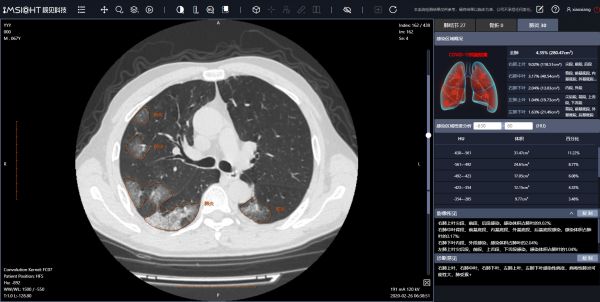

目前只要患者在深圳市人民医院、市三院做了胸部CT扫描,都会通过我们的AI系统进行自动计算,如果发现疑似新冠病例,马上会有相应提示并定位病灶区域,以及提供必要的各类定量数据分析。目前在这两家医院,我们的系统日处理的影像量加起来大约600人次。处理一例CT的时间,仅需10-20秒。

目前我们的AI系统对新冠肺炎筛查的准确率能达到99%以上,能很好地提升筛查准确性和效率,这也是 AI辅诊类产品的两个基本特点。

新冠肺炎辅助筛查系统